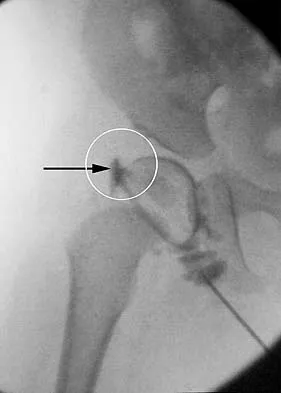

Question 100High Yield

A 39-year-old competitive cyclist sustains an injury to her left hip in a fall. Gadolinium arthrography, with an accompanying MRI scan, is shown in Figure 31. A cleft, or defect, identified by the arrow, indicates a detachment of the

Explanation